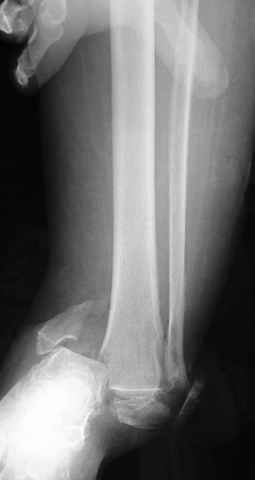

Pilon fracture:

-Появляется ориентир и остов, на чем можно строить восстановление, почему сперва малоберцовую, впервые обьяснили и описали (Pylon type and Ankle fractures) в середине 50х Rienau и Gay.

Восстановливая длину и ротацию малоберцовой кости, затем относительно легче произвести реставрацию остальных элементов перелома дистального эпиметафиза болшеберцовой кости.

конец малоберцевой кости, к нему прикрепляется латеральный суставной фрагмент дистального эпиметафиза большеберцовой кости (как на снимке)

и таранная кость, которые при репозиции малоберцовой кости репонируются автоматически.